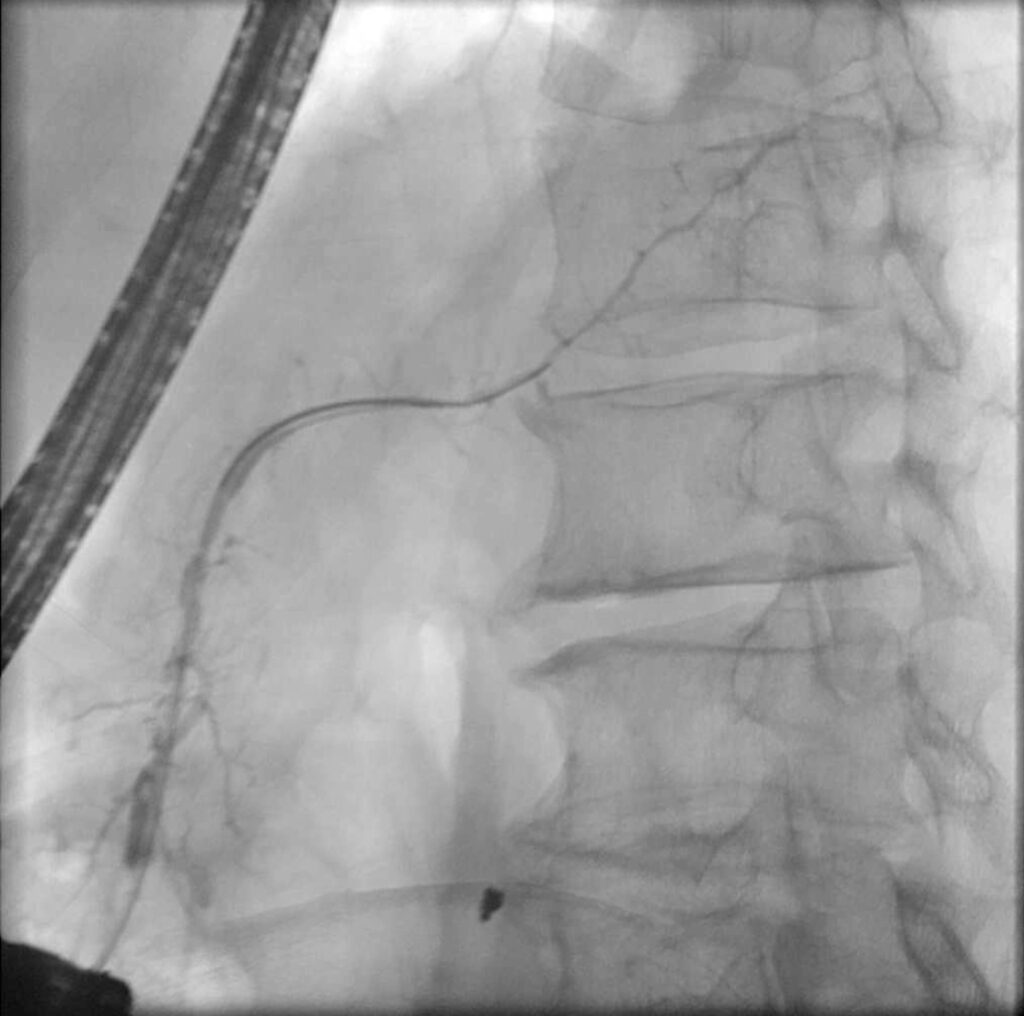

In der anschließenden ERP zeigte sich ein normal weiter Pankreasgang im Kopfbereich, im Pankreaskorpus und -schwanz mit filiformer, irregulärer Verengung. Die Nebenäste 1. Ordnung stellten sich hier regelrecht ohne Abbruch der Kontrastierung dar.